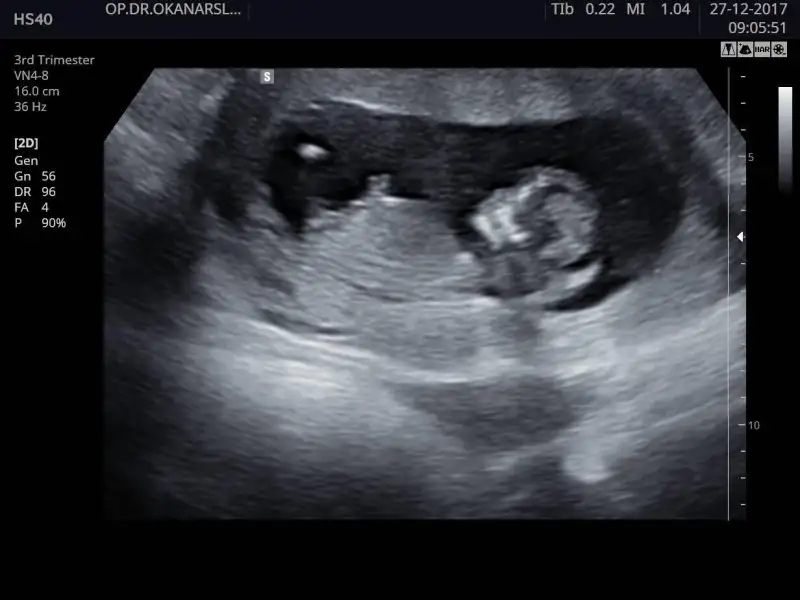

Merhaba, ultrason görüntülerinde sat'a göre 11+4 üz.

cinsiyet tahmini yapabilecek olan var mı:)

IMG_4481.webp IMG_4475.webp IMG_4476.webp IMG_4483.webp